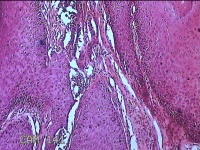

头部肿物

性别

男

年龄

21岁

临床诊断

头皮肿物

一般病史

发现头部结节10余年,无明显疼痛及不适。

标本名称

头部结节

大体所见

灰白暗红色带皮肤样结节1.5x1.3x0.3cm一个,切开结节呈实性,切面灰白粉红色,质软。